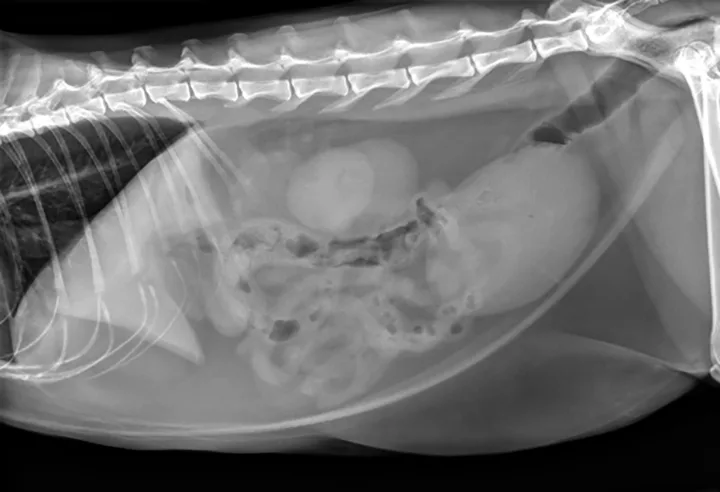

Additional diagnostic tests included abdominal ultrasound (Figure 2) and computed tomography (CT) scan with IV contrast media (Figure 3).

Figure 3. There is a filling defect taking up the majority of the lumen of the urinary bladder as evidenced by only a thin strip of positive contrast medium present in the periphery of the urinary bladder.